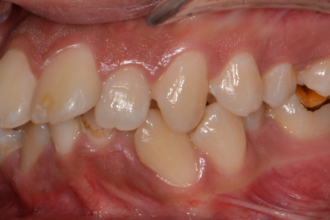

치아교정

굿프렌즈 치과 임상 케이스